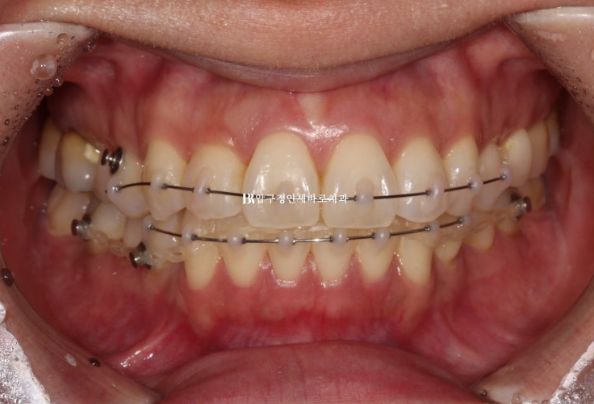

24.01

This is the appearance in the fourth month after treatment began.

Interproximal reduction was also performed for front-tooth alignment, and auxiliary appliances and elastic bands were used to eliminate the spaces that formed.

The blue resin on the molars is a bite block, also called an occlusal pad.

It temporarily raises the bite so that the front teeth do not touch.

It is not commonly used in front-tooth partial orthodontic treatment, but we proceeded with it considering the patient’s situation and the tight schedule.

Bite blocks attached to the molars are often used in full orthodontic treatment, but if used for too long, the teeth in that area can become intruded into the bone, causing the bite to open as a side effect.

Because this was short-term partial orthodontic treatment for the front teeth, the bite blocks were used for only 3 months, and after removal, the occlusion in this area remained well maintained.